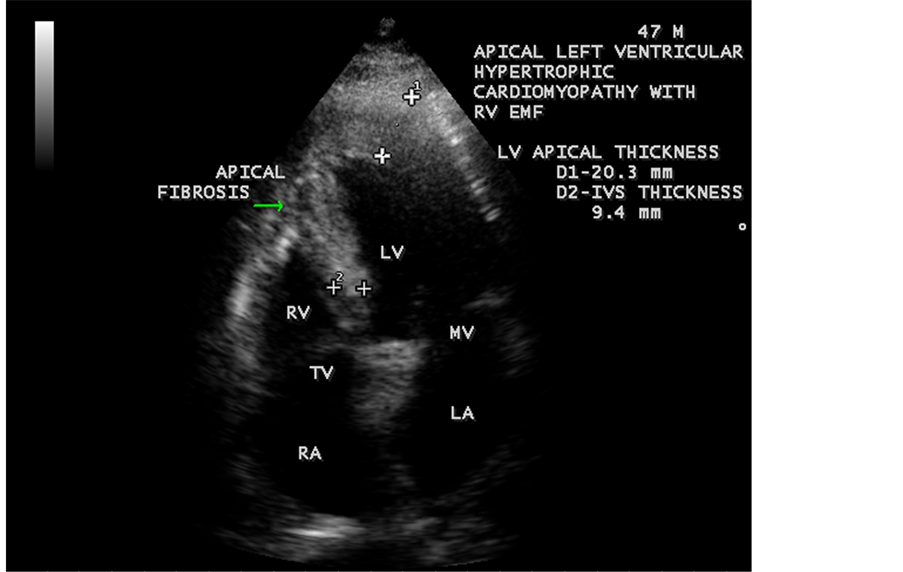

Figure 61. RV EMF with Apical left ventricular hypertrophic cardiomyopathy in a 47-year-old male. LV-spade shaped with ECG changes of LVH (left ventricular hypertrophy) pattern.

ventricle”) in a 16-year-old female as shown in Figure 50 to Figure 53 were detected. RV EMF with rheumatic involvement of mitral valve as shown in Figure 54 and Figure 55 in a 44-year-old female and in Figure 63 in a 55-year old female. Biatrial enlargement due to rheumatic atrioventricular (AV) valves (mitral and tricuspid) involvement characterized by stenosis of the valves are illustrated in Figure 56 to Figure 59 in a 54-year-old female and it is differentiated from EMF which is characterized by AV valve regurgitation as shown in Figure 34 and Figure 60. RV EMF associated with thickening and fibrosis of moderator band in a 16-year-old female was shown in Figure 46. RV EMF associated with apical left ventricular hypertrophic cardiomyopathy was shown in a 47-year-old male as in Figure 61 and in a 65-year-old female as in Figure 62.